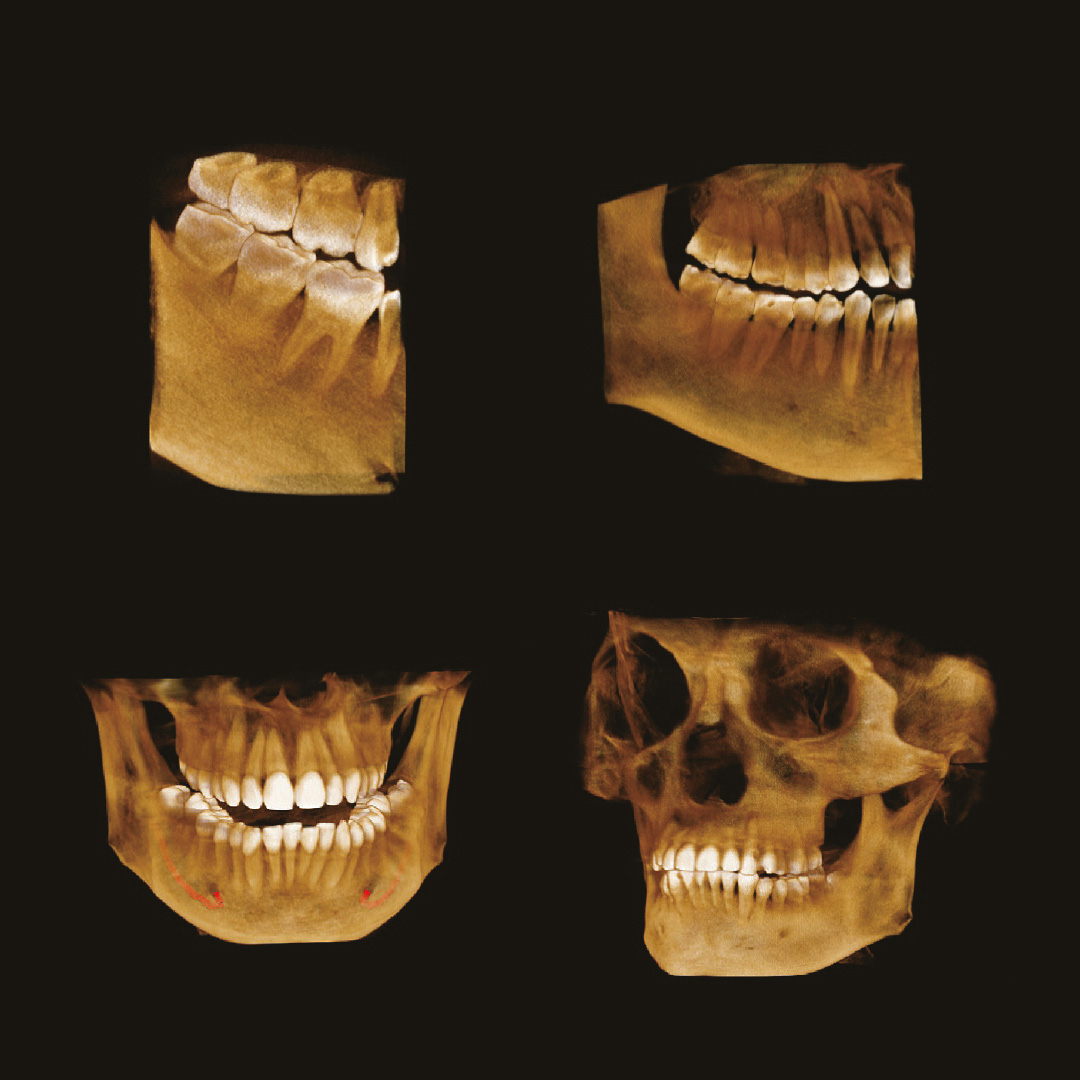

Простое и привычное ПО Triana

Программное обеспечение TRIANA обладает всем необходимым функционалом, необходимым для постановки диагноза и планирования лечения врачом-стоматологом.

Алгоритм уменьшения вторичного излучения от металлов

Умная Функция Уменьшения Артефактов от Металла (Smart Metal Artifact Reduction Function) – позволяет минимизировать артефакты от вторичного излучения металлов и получить необходимую диагностическую информацию для постановки корректного диагноза, а также планирования и контроля проведенного лечения.